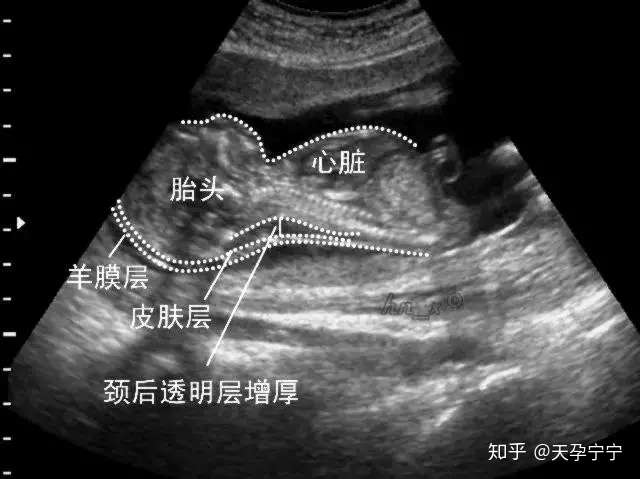

即颈项透明层,指胎儿颈后皮下组织液内液体积聚的厚度

nt就是检查胎儿颈项透明层,查看胎儿颈后皮下组织液内液体积聚的厚度

nt即颈项透明层,指胎儿颈后皮下组织液内液体积聚的厚度,反映在超声声

皮肤下的液体则看起来是黑色,所以颈后透明带厚度就是指

nt就是颈项透明层,胎儿脖子后面的一个透明带,使用超声波查看胎儿的nt